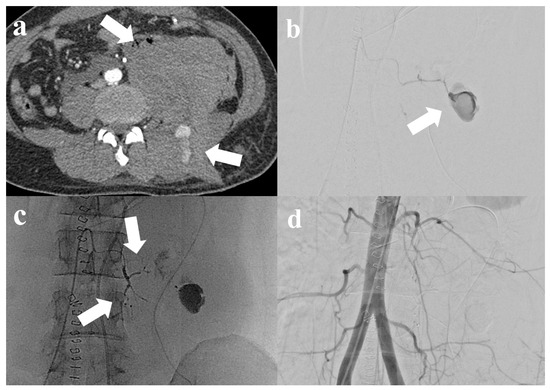

| M/29 | Neurofibromatosis | TG (Collision) | N | 103 | 1.05 | Y/Y | Left 1st, 3rd, and 4th lumbar artery (1st session) and left 2nd lumbar artery (2nd session) | 5.1 | 10 | Y → Y | 70 | Y | Clinical improvement after subsequent 2nd transarterial embolization (rebleeding from another artery and embolization was successfully performed) |